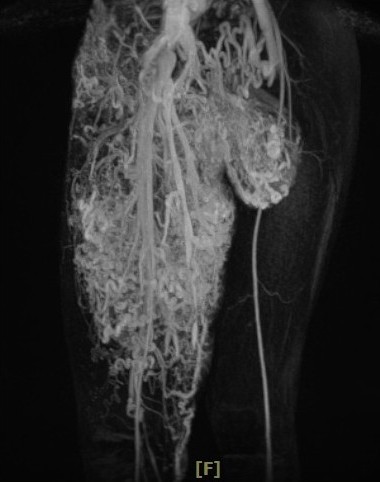

小班克的所有檢查順利完成,十一月六日,在陳培榕副院長的召集下,召開醫療團隊會議,由陳培榕副院長召集整形暨重建外科、影像醫學部、放射腫瘤科、護理部等醫療團隊,以及社會服務室主任與顏靜曦師姊,並邀請基金會劉濟雨副執行、宗教處同仁協同參與。陳培榕副院長表示,透過血管攝影檢查,發現小班克右腿的動脈與靜脈沒有經過微血管就直接相接是「動靜脈畸形」,這是最不容易處理狀況。

李俊達主任表示,小班克除了腿間的動靜脈畸形瘤,在下腹部、鼠蹊部、大腿大部分是動靜脈畸形,也是造成右大腿腫大的原因。而大腿深部的動脈與靜脈連接在一起,加上包覆大腿皮膚表層的微血管畸形面積很大,若使用雷射方式移除,得進行十次以上的雷射手術,還可能引起大出血;另一種治療方式則是使用栓塞手術,但可能會造成皮膚潰爛或引起併發症,若要全部移除是較為困難。

為了找出適合小班克的治療方式,李俊達主任及整形外科團隊也與陳明庭教授、戴浩志主任、臺大醫院影像醫學部腹部影像診斷科梁博欽主任多次討論,決定在十二月六日先與梁博欽主任一起為小班克進行血管栓塞手術,並請麻醉部疼痛科主任王柏凱協助,讓小班克在全身麻醉的情況下進行,以降低小班克的恐懼,李俊達主任說,目前影響小班克最大的是位於鼠蹊部的腫瘤,透過血管栓塞手術減少腫瘤的血液供給量,讓移除腫瘤術式能進行的更順利,也能避免失血過多的情況發生。